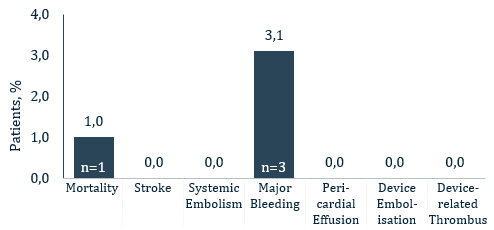

- Key 45-days safety outcomes:

- 1% all-cause death

- 0% all stroke

- 0% pericardial effusion

- 0% DRT

- 0.% device embolization

- 3,1% major bleeding (BARC 3/5)

Clinical Endpoints within 45 days of follow-up

- Patient died from a cardiac arrest 10 days after an uncomplicated implant procedure. Patient had prior history of cardiac arrest as well as renal failure, CAD and stroke and the death was not considered to be related to the procedure or device

- No patients experienced a stroke, systemic embolism, pericardial effusion, device-related thrombus, device migration or embolization

- Three patients experienced major bleeding (BARC Type 3a)